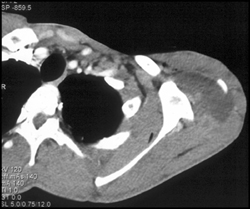

Metastases to Subcutaneous Tissues (lung Cancer Primary)